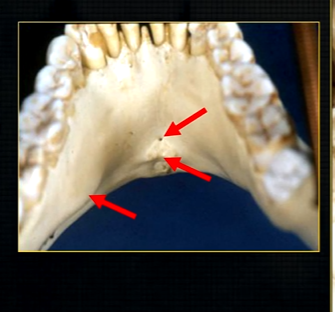

anterior lingual/inner aspect of the mandible

bony spurs

genial tubercules - muscles of the tongue and neck attach here

lingual pit

mylohyoid ridge - mylohyoid attaches to form the floor of mouth

lower occlusal

small bony spurs of the genial tubercles